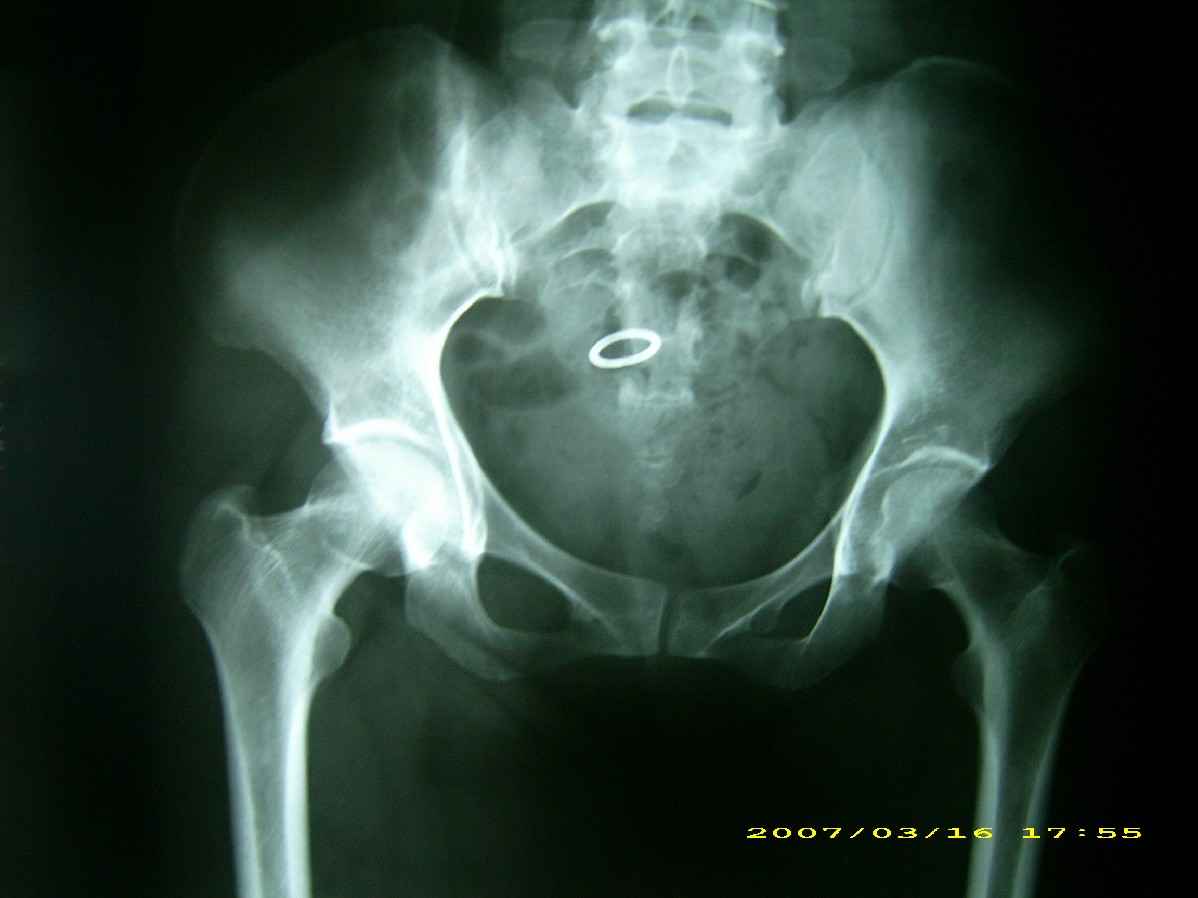

患者,女,因外伤就诊。摄骨盆及右股骨。当时报告骨盆未见明显异常,右股骨中段粉碎性骨折。五天后行股骨中段骨折内固定手术,术中摄床边片示股骨颈骨折。现把术前和术中图像上传。请大家高诊,分析股骨颈骨折是术前漏诊还是其他原因。术前骨盆片右股骨颈显示欠佳是由于股骨中段骨折无法将股骨颈完全显示。

术前片示右股骨颈未见明显骨折征象。如果事先有骨折,由于投照位置原因,骨折线也是完全有可能被挡住重叠而看不见的(并且本例骨折对位良好,更有可能看不到)。所以要凭此判断述前是否有骨折不容易

从上传的照片来看,术前无法诊断骨折。可能是投照角度的问题。

术前所照的片子体位好象有点不标准,右侧股骨颈显示不是很好,没有完全展开,所以不好说术前就一定没有骨折的情况.

楼主给我们大家提供了非常好的片子,感谢!该片股骨颈的骨折术前看不到骨折。这个和体位也有关,但是我们都知道,那些标准的体位是给健康人设计的,外伤比较重的往往都无法标准投照。不知道同行们有没有这样一种感受:发现明显的问题了,就心里比较踏实了,舒坦了,就不容易对其它细节仔细观察了。如果没有发现明显的问题,就仔细的翻来覆去的看。所以这个片子给我们很大的教训:仔细阅片!即便是已经发现问题了。如果非要给鸡蛋里面挑骨头,我认为楼主忽略了右髋关节囊的肿胀,诊断报告应该提一下。外伤的病人我最怕股骨颈的漏诊,一般我都要看软组织。我是一个小医院的,我深有感触,发现骨折不是功劳,而漏诊却是事故,还遭受别人耻笑:放射科的连骨头断没断都看不出来!